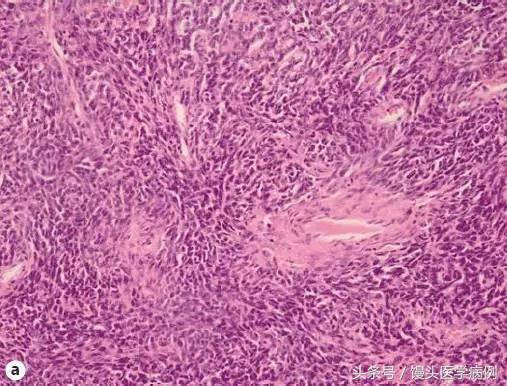

图 3 a 恶性布伦纳瘤策划学切片(HE 染色法 250 倍);b 恶性布伦纳瘤细胞学涂片,可见到许多乳头状细胞簇,落单的异型性细胞,背景为坏死策划(巴氏染色法 250 倍)